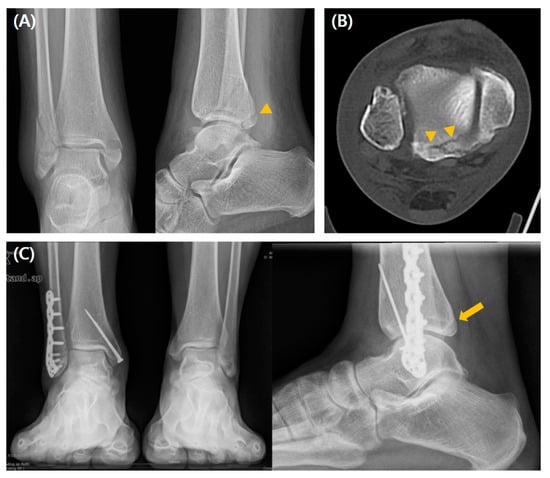

3.1. Comparison Between the Fixation and Non-Fixation Groups Within Type 1 Fracture

The intercalary fragment (ICF) assessed by preoperative CT was more frequently observed in the fixation group (p < 0.001). There were no significant postoperative intergroup differences in reduction quality assessed by immediate postoperative CT, residual step-off, or PTOA development. Moreover, there were no significant intergroup differences in the clinical values, including mean AOFAS, OMAS, FAOS, or VAS scores at the final follow-up. Postoperative complications occurred more frequently in the fixation group (37% vs. 18.6%, p = 0.008) (Table 1). A radiographic case example of a type 1 fracture is depicted in Figure 3.

Figure 3. A case of a 56-year-old man who underwent conservative management for type 1 PMF. (A) Preoperative radiographs show a fracture line (arrowhead), and (B) preoperative CT scan images show a posterior malleolar fragment representing a type 1 fracture line (arrowheads) without the ICF. (C) Weight-bearing radiographs obtained 3 years postoperatively show acceptable reduction and bone healing (arrow).